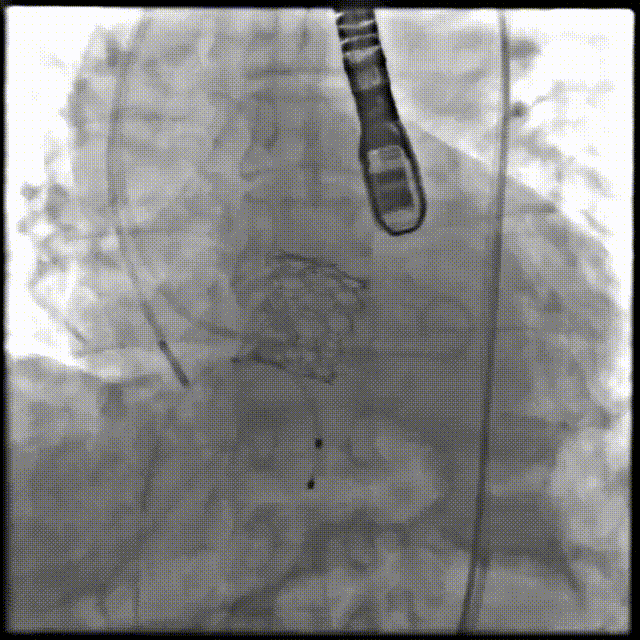

术前造影

术后造影